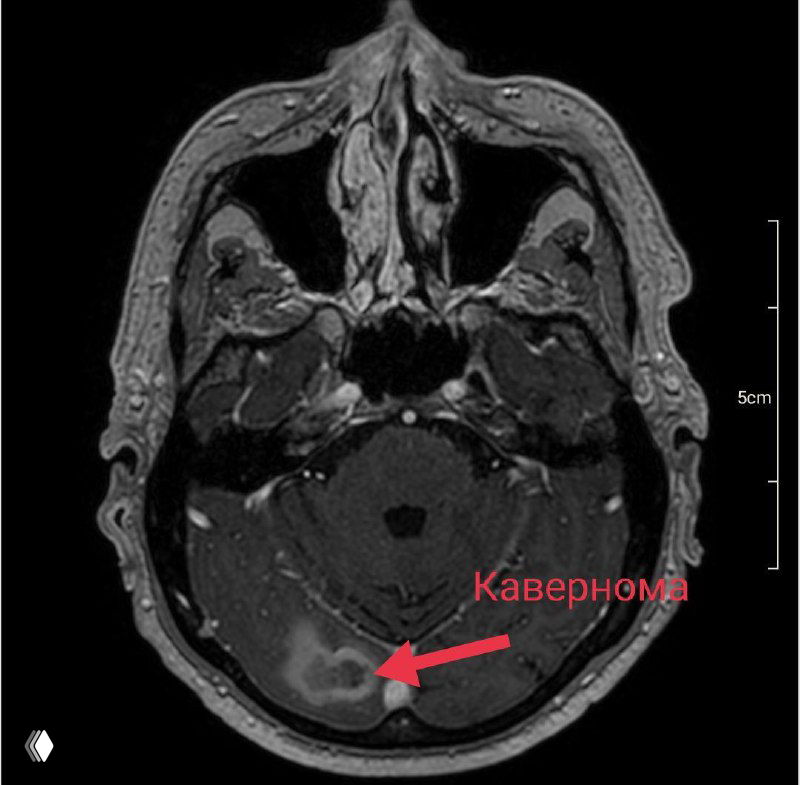

Парадокс, но некоторые каверномы после кровоизлияния уменьшаются в размерах или становятся менее симптомными.

Но это не повод расслабляться - риск повторного кровотечения остаётся и составляет более 30%.

Удаление субкортикальных симптомных каверном в настоящее время безопасный и радикальный метод лечения.